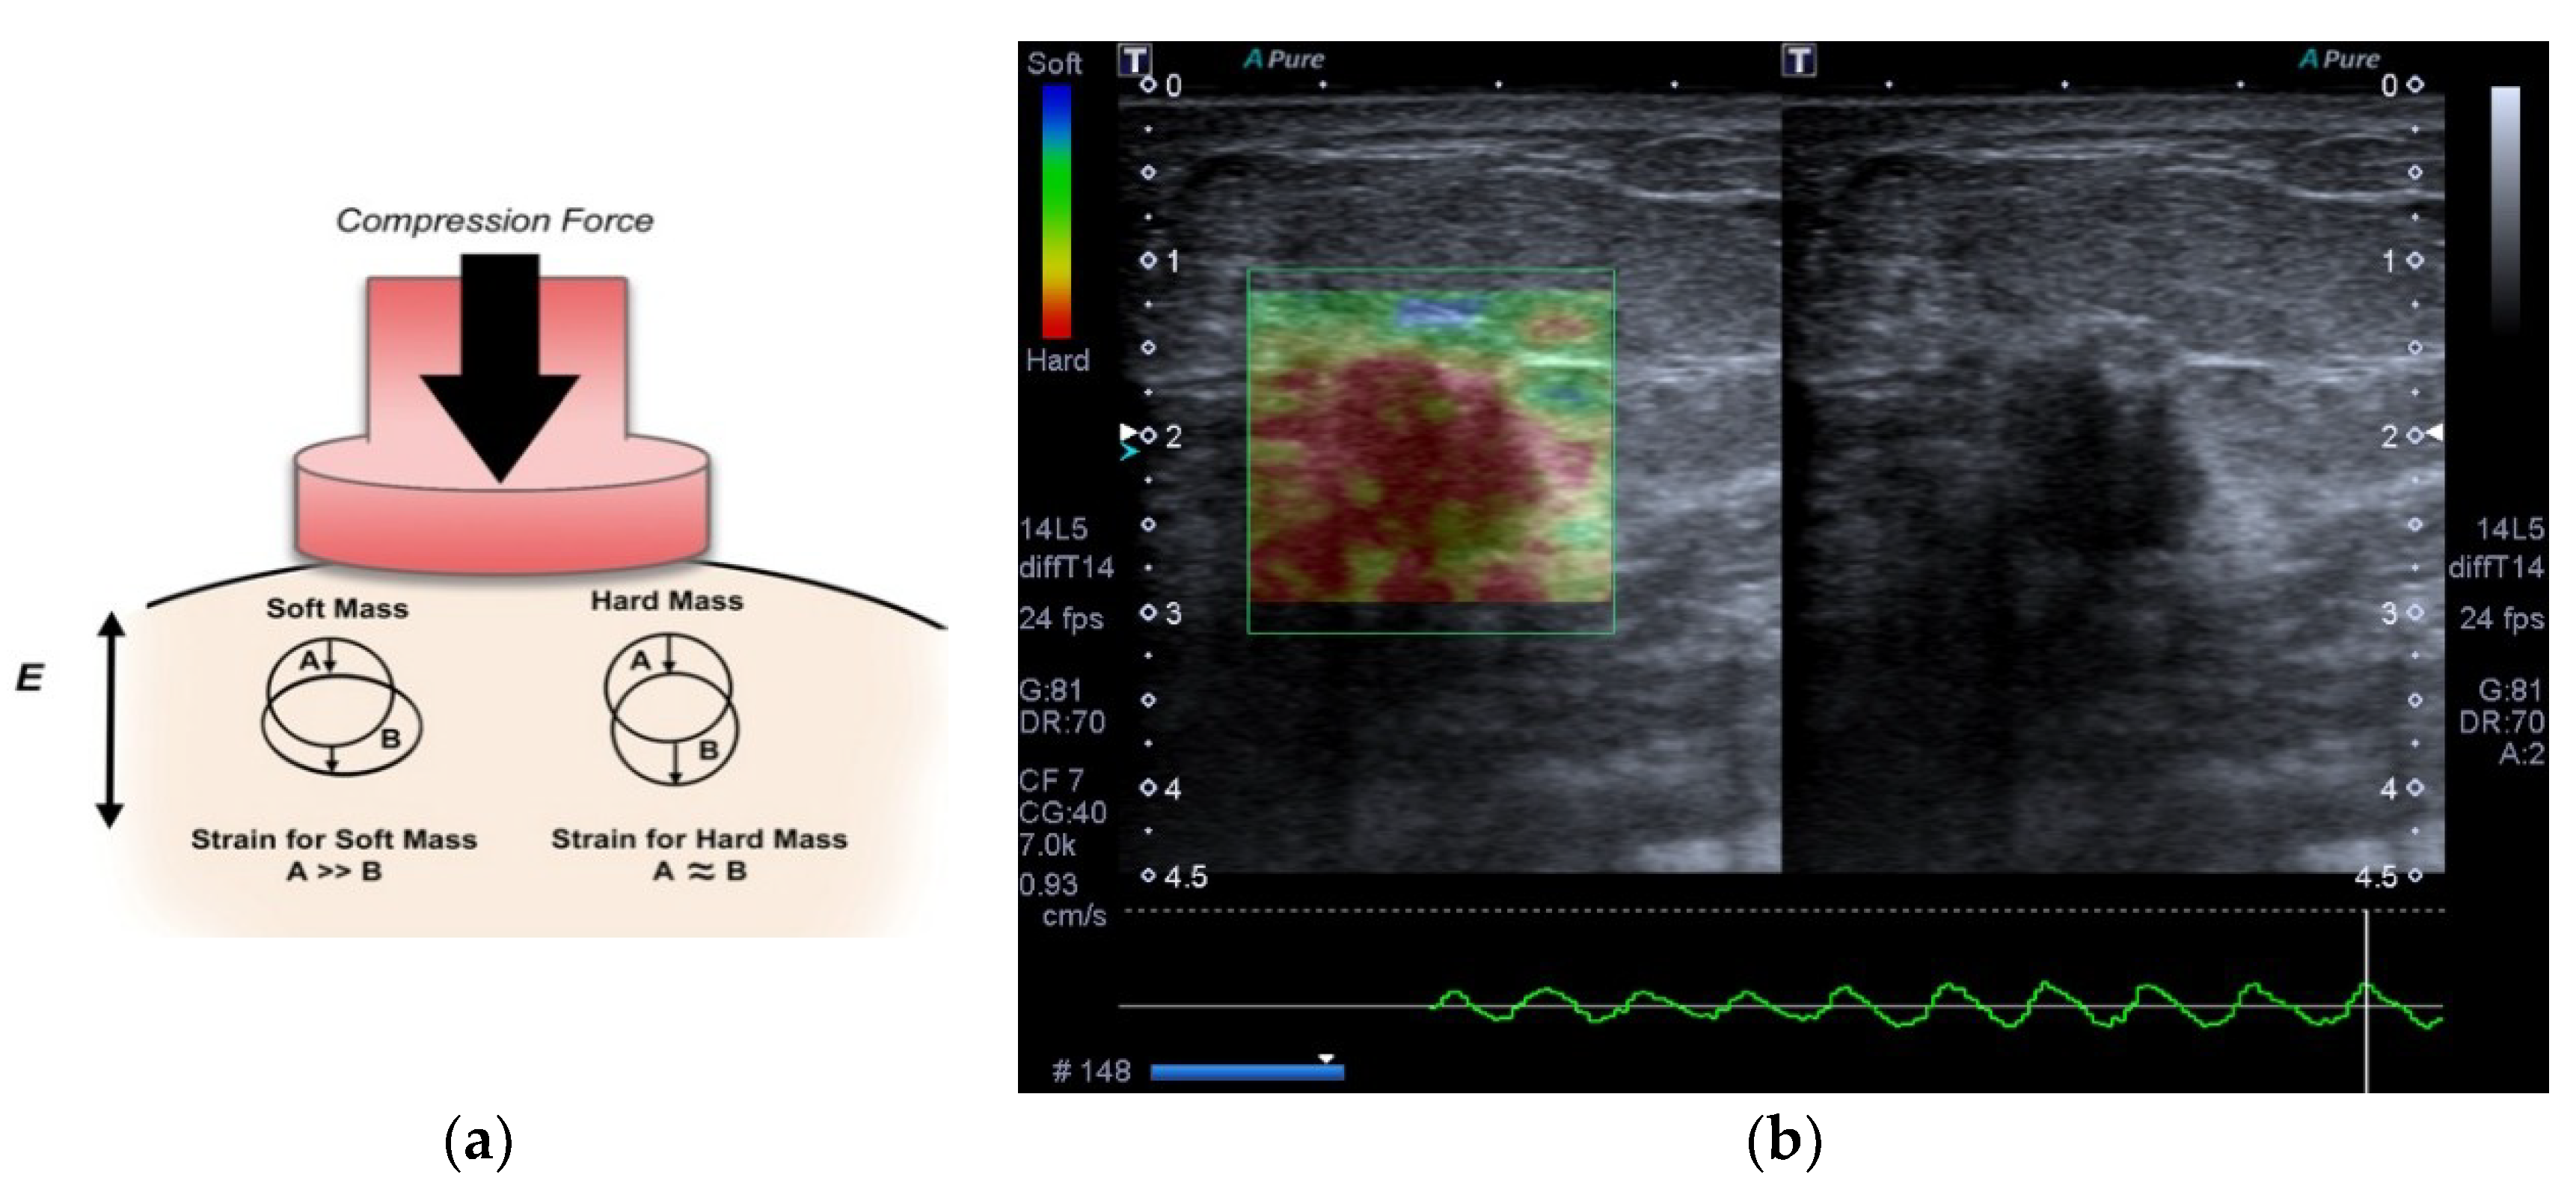

Strain elastography (SE) is a type of elastography based on applying a compressive force to the breast in order to assess the tendency of tissue to resist to deformation with an applied force, or to resume its original shape after removal of the force, thus providing a value of lesion stiffness in relation to the surrounding tissue [2,9,10,11]. Elastography is widely used to evaluate lesions detected at breast cancer screening [12,13]. The strain data are converted to images, often in the form of a color overlay upon the corresponding B-mode image, or a gray-scale image displayed next to the corresponding B-mode image. The side by side display without overlay allows a better appreciation of patterns of stiffness and softness within lesions as a result of the higher image contrast achievable when image transparency is not an issue [6,11]. In general, the elasticity information is displayed in the form of a gray image. The dark region of an elastogram indicates the hard tissue (no strain) and the bright one indicates the soft tissue (high strain). However, images can also be displayed in color scale, in which the color spectrum typically goes from blue tissue (high strain) to red (no strain), that is, from the soft to hard lesions, respectively, with an intermediate level green (with a medium level of strain). The color scale may vary depending on the ultrasound manufacturer [14]. Many studies have reported that it can increase the specificity of conventional B-mode ultrasound in differentiating benign from malignant masses, reducing the number of benign breast biopsy results [2,15]. An example of SE based compression process is shown in Figure 1.

Figure 1.

Strain elastography measures tissue displacement as a consequence of an applied initial compression. (a) Behavior of the soft and hard tissue after a compressive force. The displacement of the first is larger in soft tissue than hard tissue. (b) Image of invasive ductal carcinoma in a 56-year-old woman with strain elastography on left and B-mode ultrasound on right.